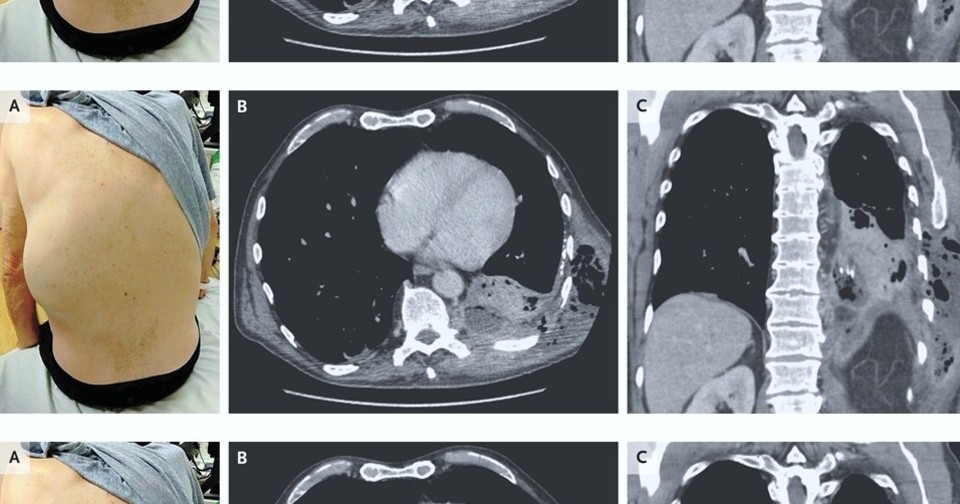

К американским врачам обратился 66-летний мужчина с хронической обструктивной болезнью легких с одышкой и кашлем в течение двух недель, а также болями в левом боку в течение пяти дней. За два дня до обращения он отметил появление и быстрое увеличение опухоли на левом боку. Обследование показало, что у пациента развилось редкое осложнение эмпиемы плевры, при котором гной не собирается в плевральной полости, а прорывает париетальную плевру и распространяется в соседние области. У мужчины он попал на левую заднюю боковую стенку грудной клетки. Случай описан в The New England Journal of Medicine.

При первичном осмотре Адеолува Айоола (Adeoluwa Ayoola) и Крешник Зейнуллаху (Kreshnik Zejnullahu) из Калифорнийского университета выявили у пациента ослабление дыхания у основания левого легкого, а также болезненное образование на спине с левой стороны. Компьютерная томография грудной клетки показала уплотнение левой нижней доли, которое связали с небольшим многоочаговым плевральным выпотом, содержащим газ. Пациенту провели небольшую операцию и дренировали скопление гноя в грудной стенке. Больной прошел длительный курс антибактериальной терапии, и в течение шести месяцев его состояние нормализовалось.